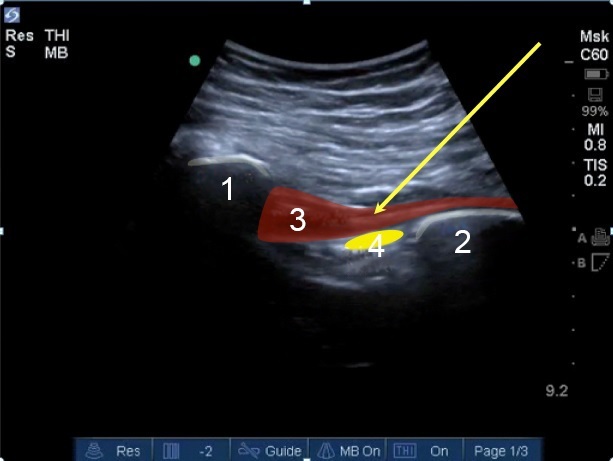

Hip Piriformis Dynamic Maneuver Image

Sacrum

Ischium

Piriformis

Sciatic Nerve